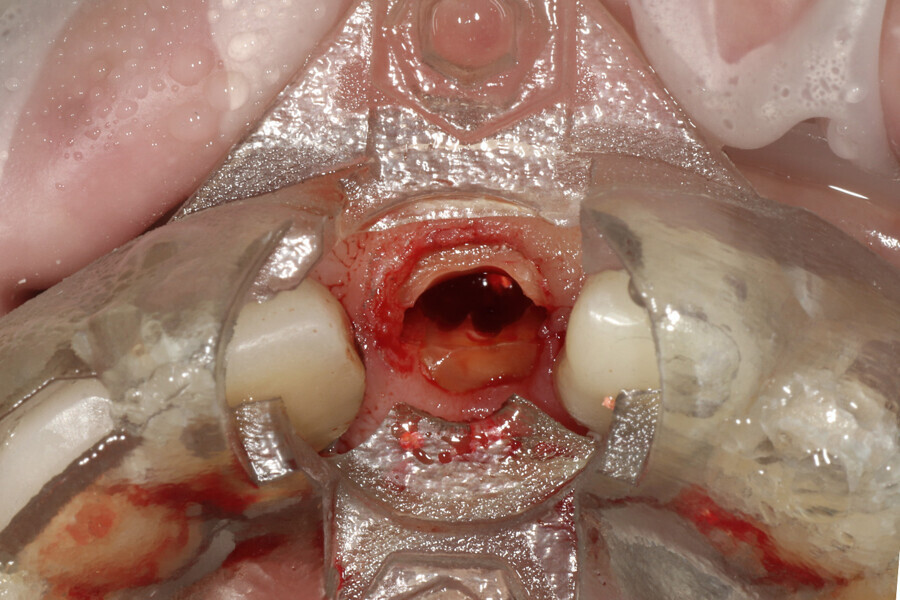

Fig. 12a: A post fracture presenting in the left central incisor, requiring extraction.

Fig. 12b: The occlusal view illustrated the cervical tissue volume and contours.